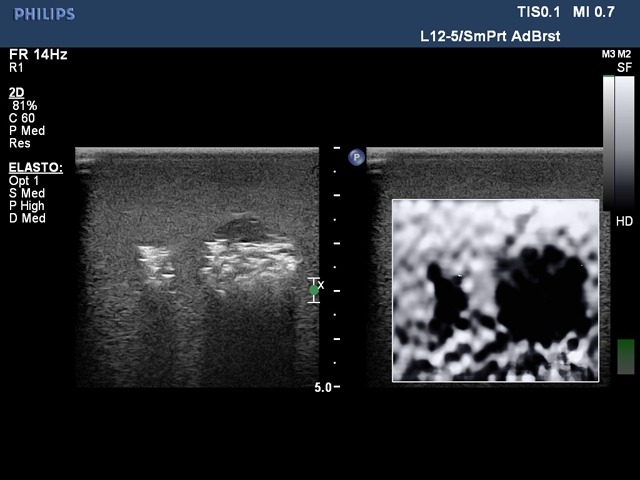

乳房超声弹性成像训练模型给用户提供了一个很好的培训平台,用户可以通过使用本产品练习乳腺弹性成像所需的技能。模型内部的肿块大小不同,便于学生先练习较大病灶的识别和扫描,待熟练后再练习扫描尺寸更小的病灶。